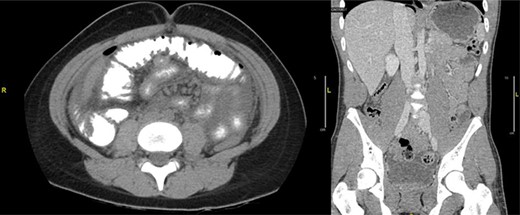

Case 1: A 14-year-old boy with a 2-day history of mild abdominal pain presented to the emergency department (ED) within 6 hours of sudden-onset severe abdominal pain, persistent, mostly in the periumbilical area. He denied nausea, vomiting, diarrhea, fever, melena and hematochezia. Past medical history only significant for ADHD on Adderall. On exam, he appeared in severe distress, with normal vital signs, diffuse abdominal rebound tenderness and rigidity. Laboratories revealed elevated white blood cell count (WBC) of 14.900/L and normal C-reactive protein. Abdominal ultrasound was unremarkable, but since the concern for acute abdomen, a computer tomography (CT) of the abdomen and pelvis was obtained, demonstrating a large pneumoperitoneum predominantly in the upper abdomen suggestive of perforated viscus (Fig. 1).

(a) CT abdomen and pelvis axial view. (b) CT abdomen and pelvis coronal view: there is a large pneumoperitoneum predominantly in the upper abdomen.